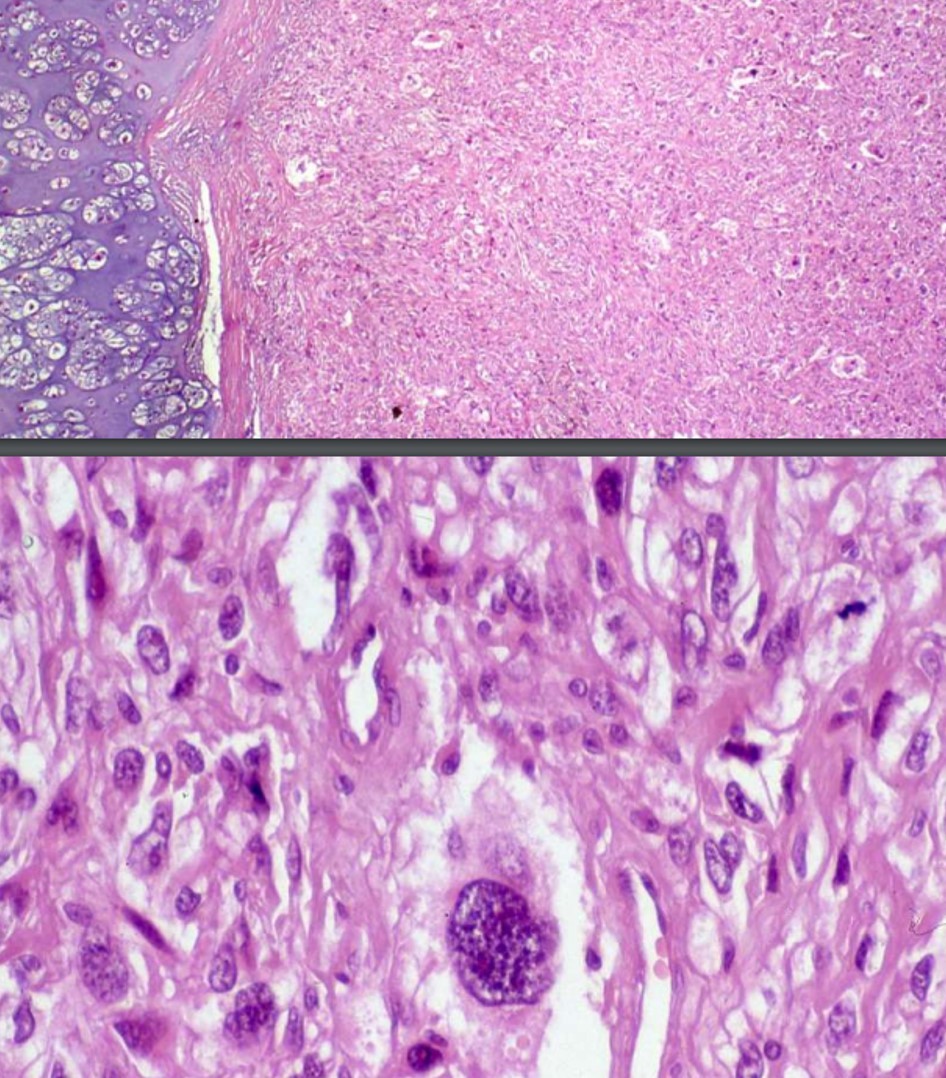

CONVENTIONAL OSTEOSARCOMA

TELANGIECTATIC OSTEOSARCOMA

SMALL CELL OSTEOSARCOMA